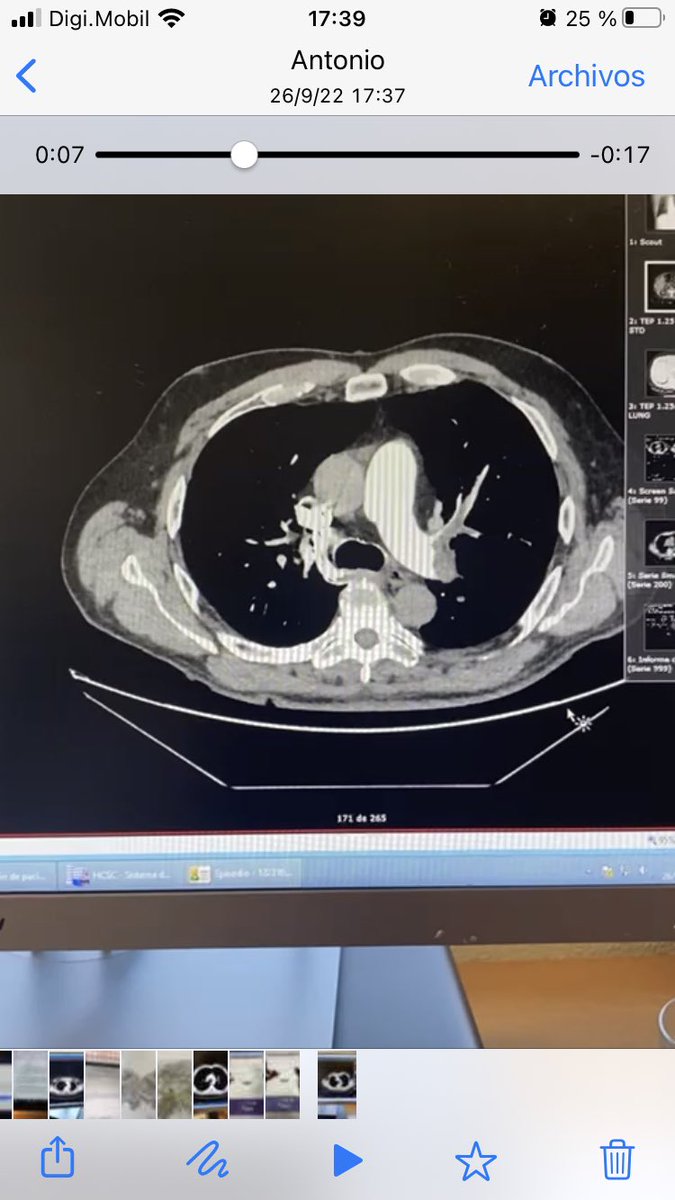

@Ana_Viana_T

Ana Viana Tejedor

3 years

Varón de 72 años, previamente sano que acude esta madrugada por disnea…